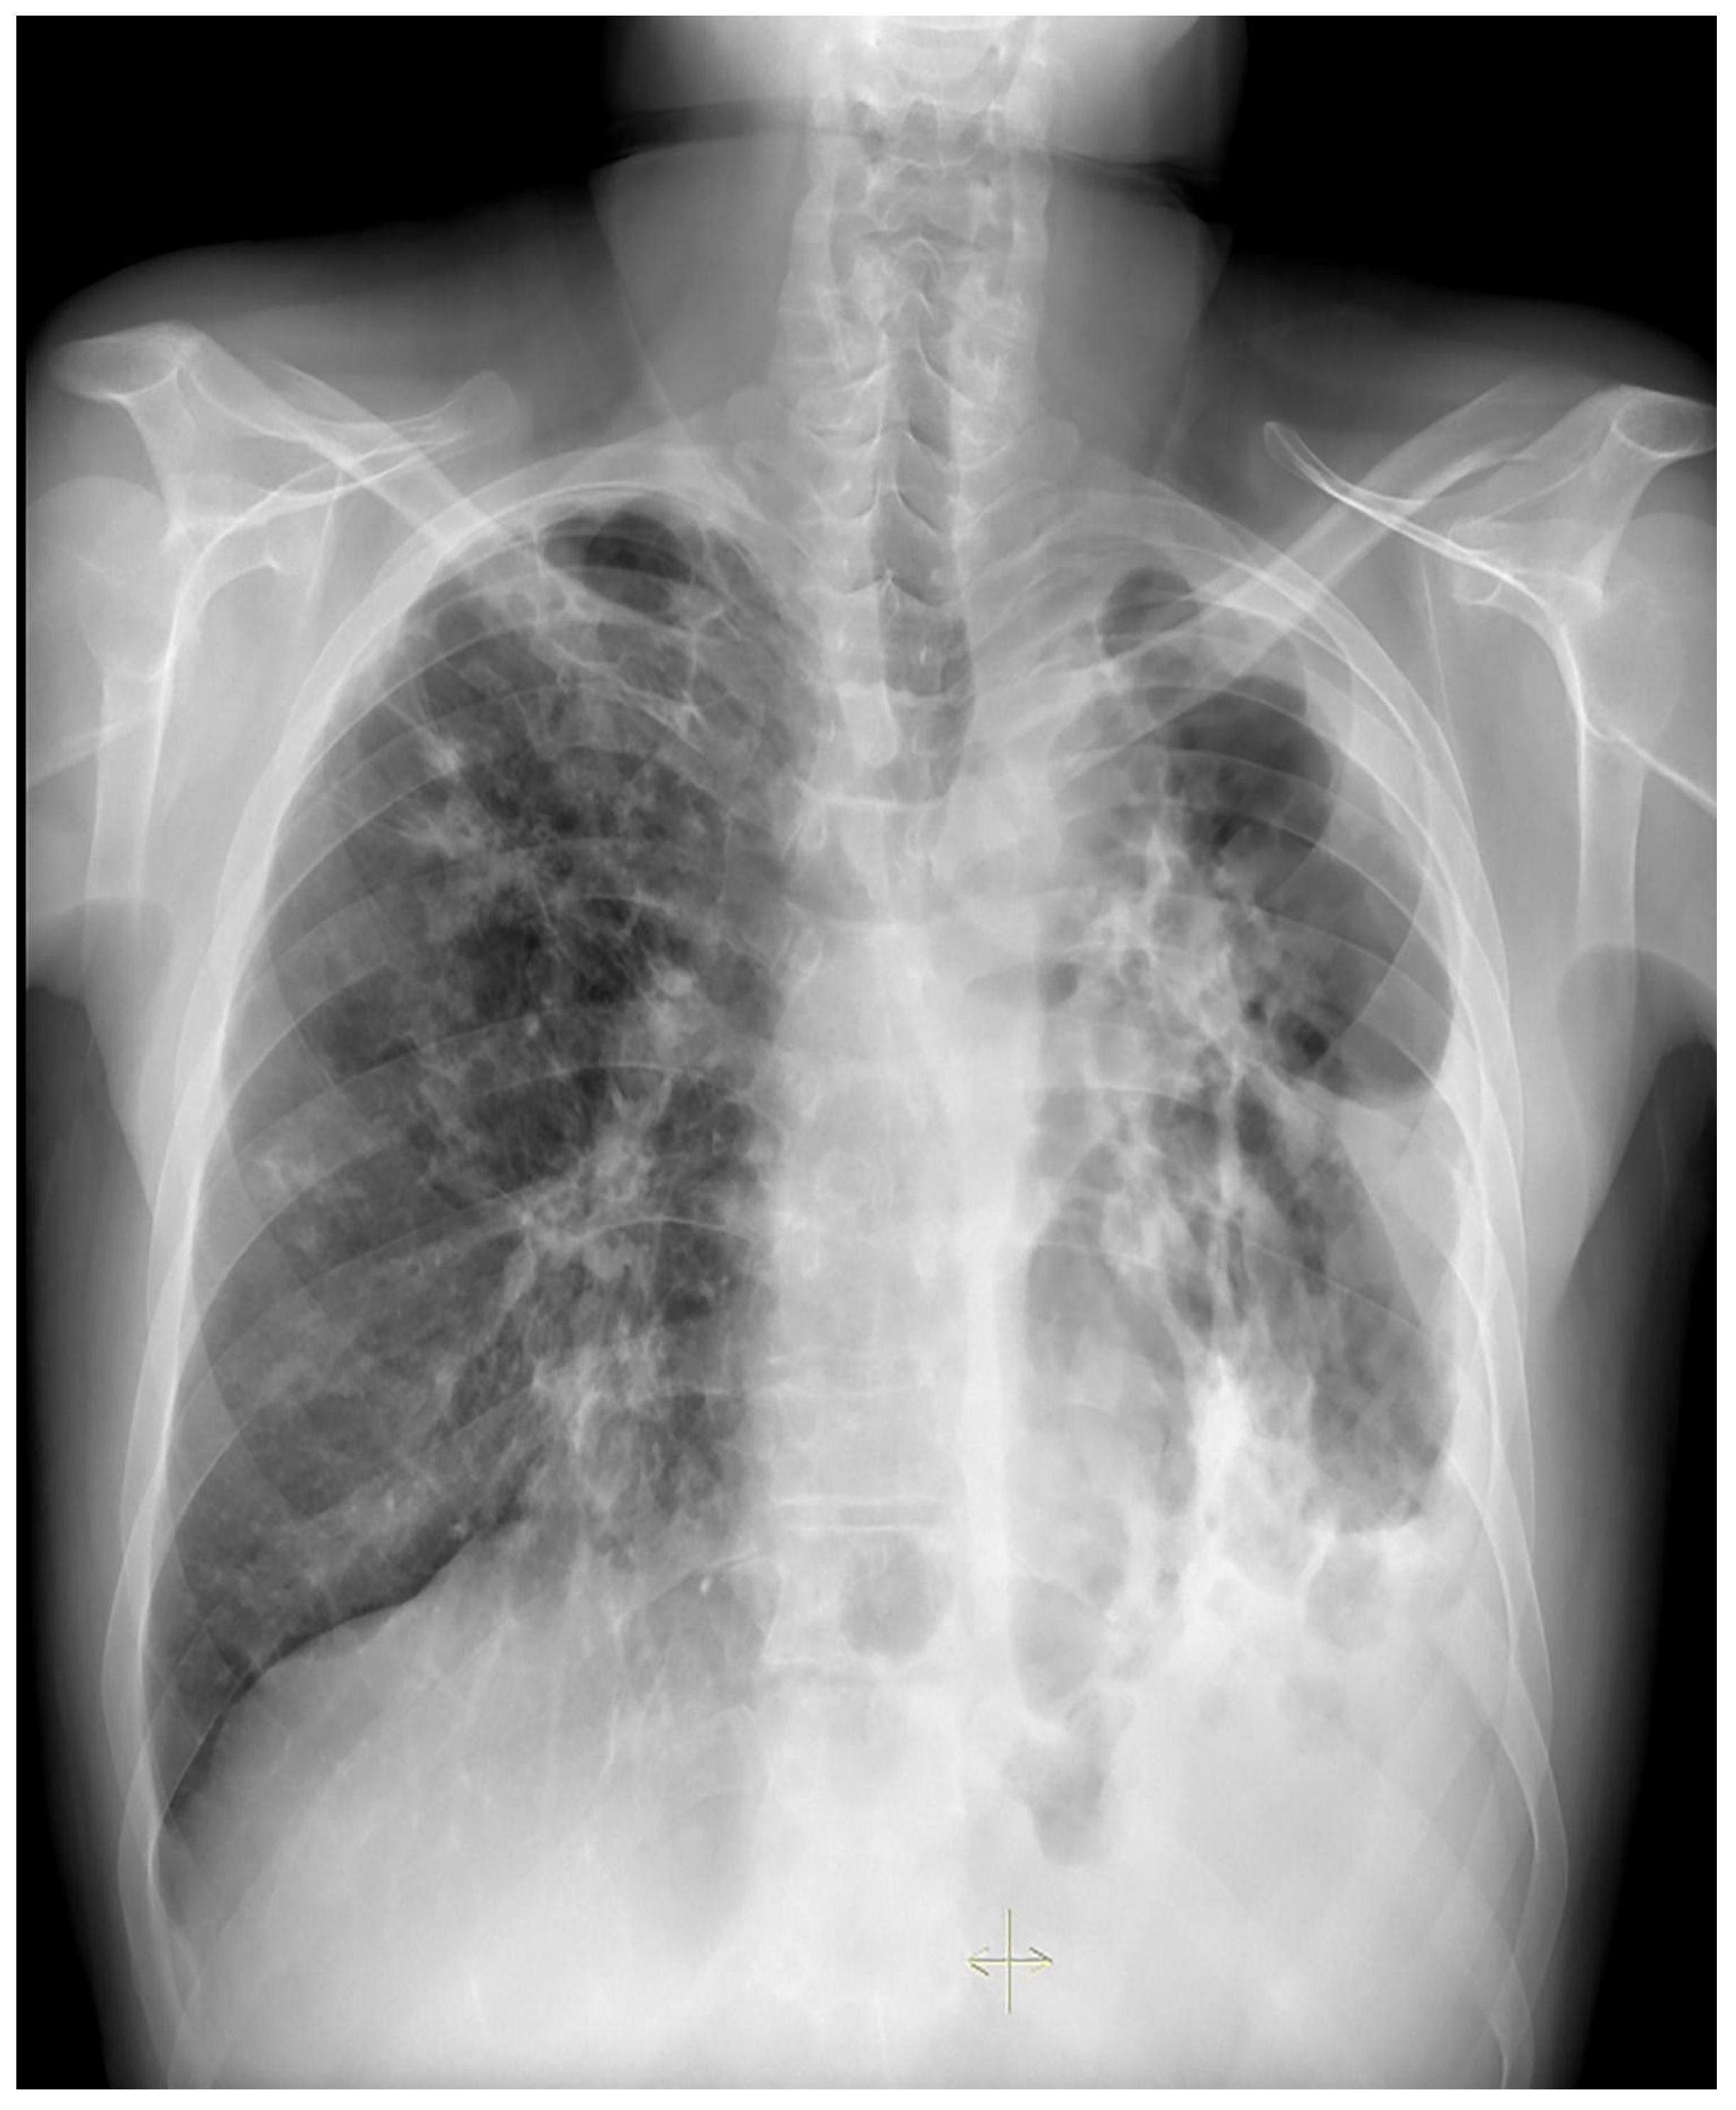

Treatment results of seven patients were reported as follows; two patients as not evaluated (returned to their home country), two patients as completion of treatment, and three patients as cured. The duration of treatments was planned as nine months, and the treatment of the patient with FQ and Z resistance (case 7) continued for 12 months. No recurrence was detected in the first-year follow-up of the five patients who could be followed. Regarding Case 4’s chest X-ray images at the beginning and the 59th day of the treatment (Figure 1 and Figure 2) and Case 7’s chest X-ray images at the beginning and the 12th month of the treatment (Figure 3 and Figure 4) a significant radiological improvement was observed.

Figure 1. Case 4, beginning of the treatment.